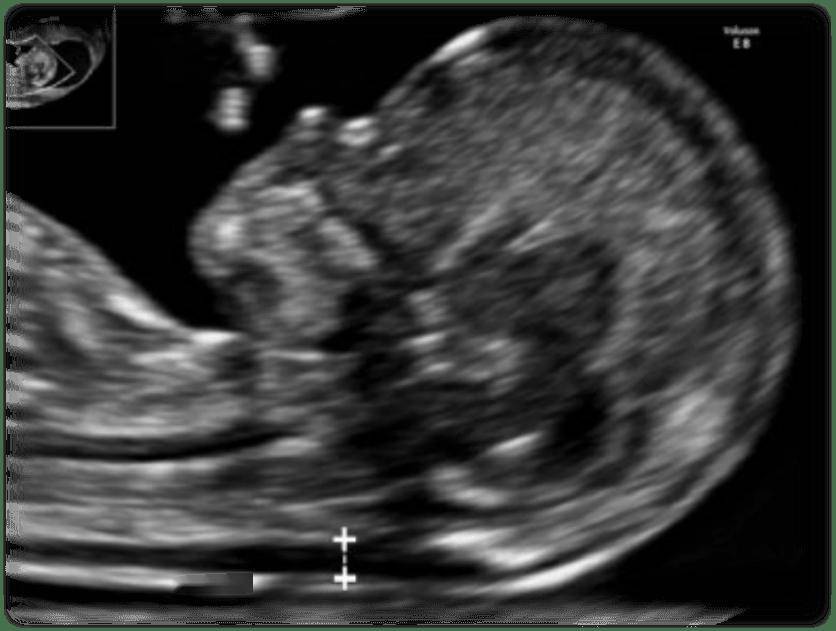

NT是胎兒頸項透明層(Nuchal Translucency)縮寫,是在孕11周至13周6天超聲下測量獲得的胎兒頸後皮膚與深部軟組織之間的薄層液性暗區的厚度,是胎兒頸部淋巴管與頸靜脈竇相通之前,由於生理性淋巴液迴流障礙,導致組織液和淋巴液在頸部短暫性積聚而成,隨著淋巴液迴流的建立,正常胎兒淋巴液順利引流入靜脈後NT會逐漸消失收藏

NT是孕11至13周6天超聲檢查內容之一,其他重要內容包括頭臀徑、鼻骨、三尖瓣血流、靜脈導管血流等收藏

圖片來自指南ISUOG Practice Guidelines: performance of first-trimester fetal ultrasound scan(2013)